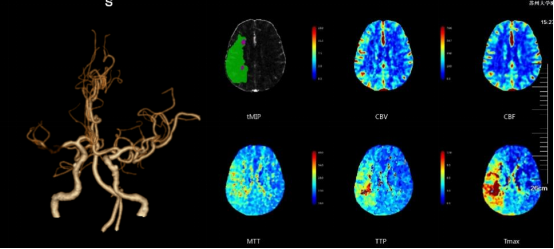

CTA+CTP:右侧大脑中动脉水平段(R-M1)管腔完全闭塞;右侧额顶颞叶缺血性灌注异常

术前PWI:右侧岛叶、颞叶、右侧脑室旁及放射冠区CBF、CBV减低,MTT、TTP较对侧延长

术后PWI:右侧岛叶、颞叶、右侧脑室旁及放射冠区血流明显改善